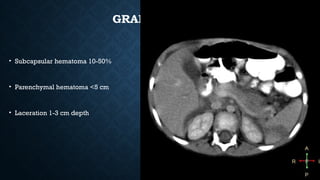

GRADE II

• Subcapsular hematoma 10-50%

• Parenchymal hematoma <5 cm

• Laceration 1-3 cm depth